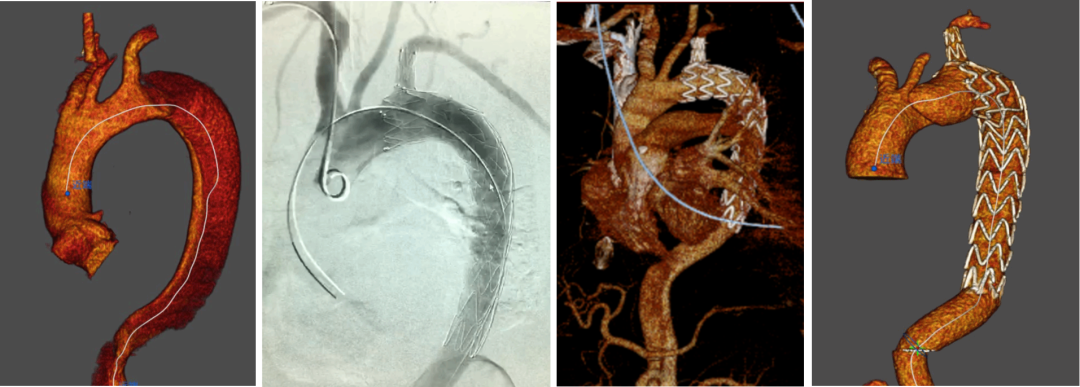

★ Case6:男,55岁, 胸痛4天入院。诊断:A型主动脉夹层

3D打印模型

分支前后体外预开窗

术毕造影

术后CTA

★ Case7:35岁, 主动脉夹层TEVAR术后( Castor 重建LSA)。4个月后出现新发破口(逆撕),累及左颈总动脉